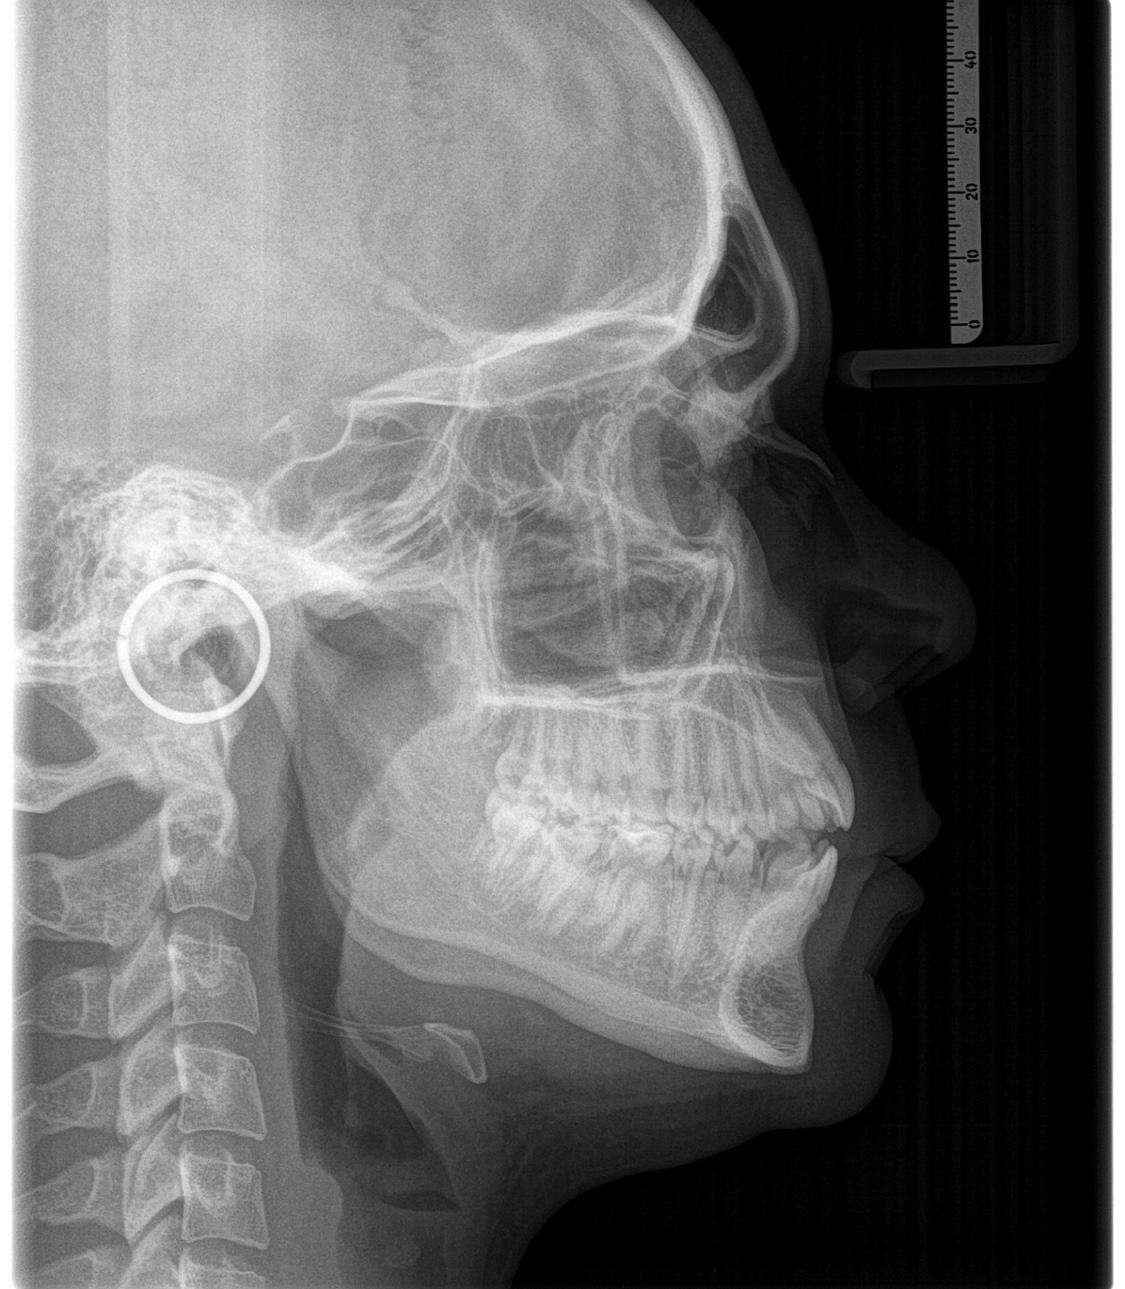

Открытый прикус, помогите разобраться